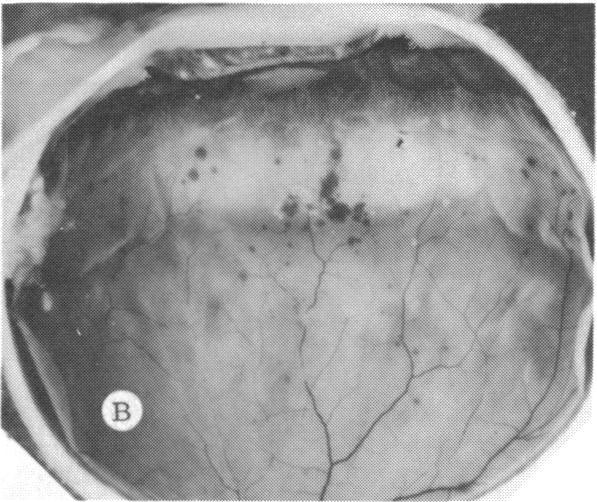

The clinical and histopathologic features of 29 eyes from 29 patients with central retinal vein occlusion (CRVO) are reported. A fresh or a recanalized thrombus was observed in each eye. This study considers the temporal aspects of the cases, and it notes the different morphologic features of the occlusion. These observations explain most of the variability of the changes observed in previous reports. We believe that these different features represent the various stages in the natural evolution of such a thrombus. The interval between CRVO and histopathologic study in our series ranged from six hours to more than 10 years. Local and systemic factors were reviewed and were found to be important in the pathogenesis of thrombus formation. Local diseases with a predisposing effect on CRVO included: glaucoma, papilledema, subdural hemorrhage, optic nerve hemorrhage, and drusen of the optic nerve head. Associated systemic diseases included: hypertension, cardiovascular and cerebrovascular disease, diabetes mellitus, and leukemia with thrombocytopenia. A fresh thrombus in the CRVO was observed in three (10.3%), and a recanalized thrombus in 26 eyes (89.7%). Endothelial-cell proliferation was a conspicuous feature in 14 (48.3%) of the eyes. Chronic inflammation in the area of the thrombus, and/or vein wall or perivenular area was observed in 14 (48.3%) of the eyes. Arterial occlusive disease was observed in seven eyes (24.6%). Cystoid macular edema was found in 26 (89.7%) of the eyes.

报告了29例视网膜中央静脉阻塞(CRVO)患者29只眼的临床和组织病理学特征。每只眼中均观察到新鲜或再通的血栓。本研究考虑了病例的时间因素,并记录了阻塞的不同形态学特征。这些观察结果解释了先前报告中观察到的变化的大部分变异性。我们认为这些不同特征代表了此类血栓自然演变的各个阶段。我们系列中CRVO与组织病理学研究之间的间隔时间从6小时到10多年不等。对局部和全身因素进行了回顾,发现它们在血栓形成的发病机制中很重要。对CRVO有 predisposing 作用的局部疾病包括:青光眼、视乳头水肿、硬膜下出血、视神经出血和视神经乳头玻璃膜疣。相关的全身疾病包括:高血压、心血管和脑血管疾病、糖尿病以及伴有血小板减少的白血病。在CRVO中观察到3只眼(10.3%)有新鲜血栓,26只眼(89.7%)有再通血栓。14只眼(48.3%)中内皮细胞增殖是一个显著特征。14只眼(48.3%)中观察到血栓区域、和/或静脉壁或静脉周围区域有慢性炎症。7只眼(24.6%)中观察到动脉闭塞性疾病。26只眼(89.7%)中发现黄斑囊样水肿。 (注:文中“predisposing”可能是“易患的”意思,但在专业医学语境中,可能有更准确特定含义,这里按常见理解翻译,具体含义需结合医学专业知识进一步确认。)